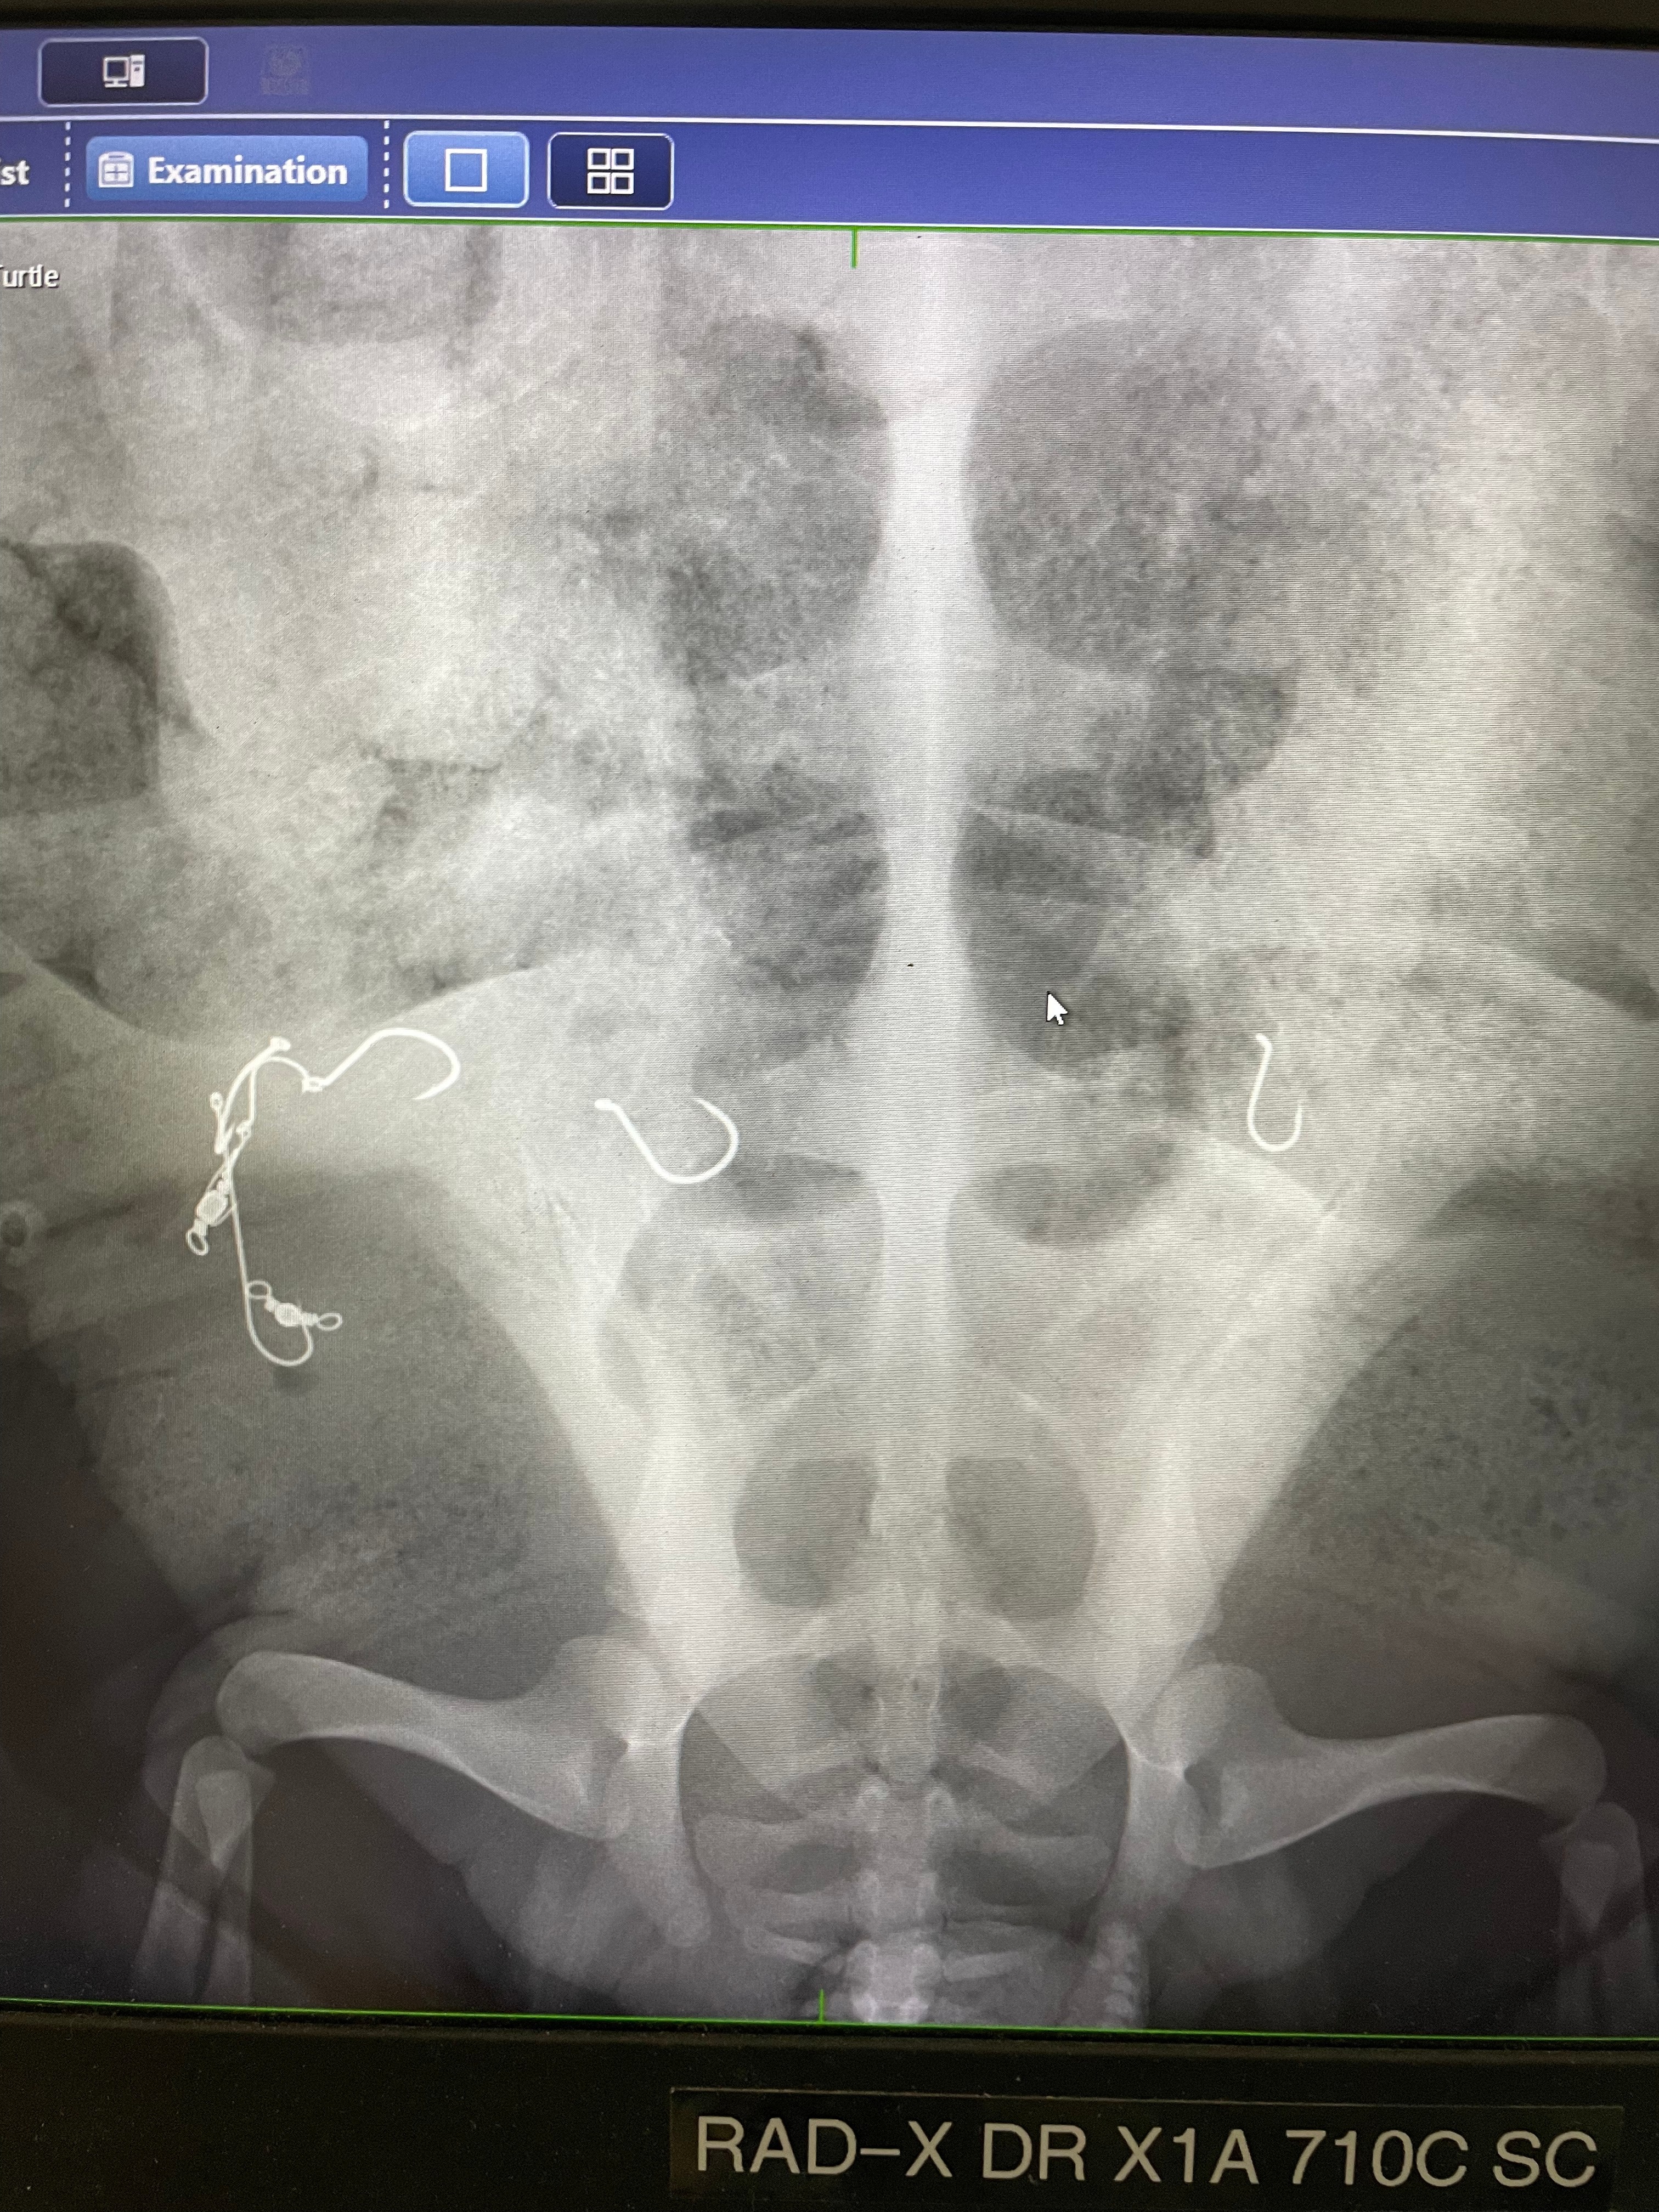

X-rays show the seven fishhooks in the turtle's intestines. (Supplied: Taronga Wildlife Hospital)

X-rays revealed seven hooks inside the turtle, including four that were in a gang-hook formation.

Parts of the turtle's intestines had been damaged by the hooks and the fishing line.